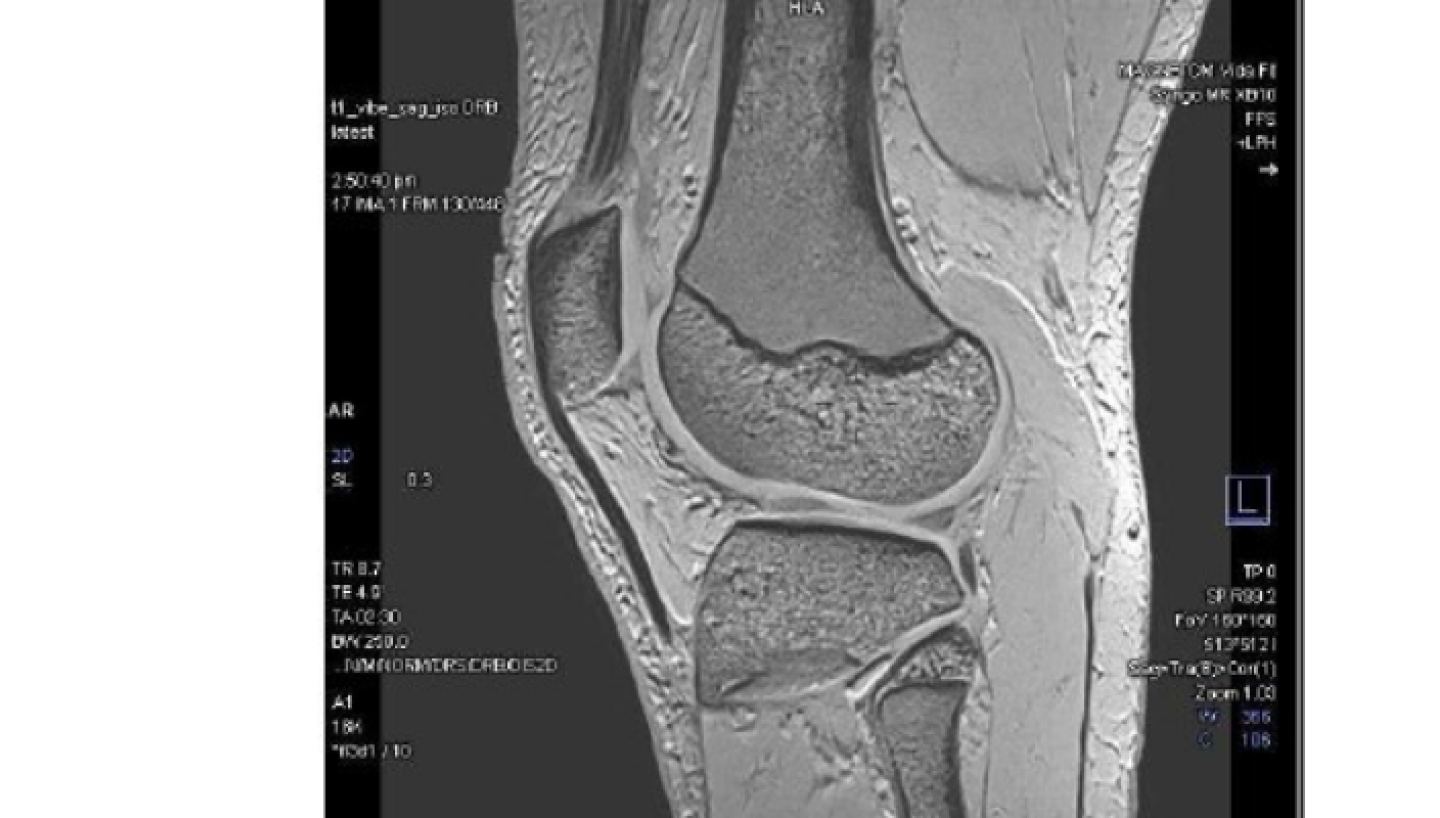

An MRI (Magnetic Resonance Imaging) is a non-invasive imaging technique that captures detailed images of the inside of your body. It allows our specialist radiologists, and your healthcare provider to clearly visualise your organs, tissues, and bones, without using ionising radiation.